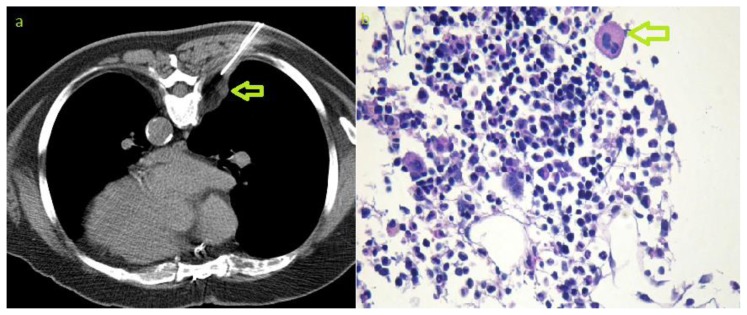

Figure 4.

70-year-old male with bilateral multifocal paravertebral extra-adrenal myelolipoma. CT-guided biopsy. a) axial non-enhanced CT obtained during biopsy procedure showing the needle that was advanced in a dorsal approach for biopsy of the paravertebral lesion (arrow). b) Photomicrography (Periodic acid Schiff stain, magnification 200x) showing bone marrow cells and megakaryocyte (arrow). Photomicrograph image courtesy of Prof. Alexander Tzankov, pathology department, University Hospital Basel, Switzerland)